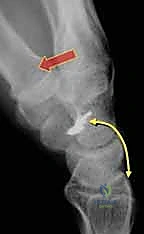

* Lateral View: Essential for measuring the scapholunate angle. An angle >60 degrees indicates significant disruption. We're aiming for 45 ± 5 degrees during reduction.

* CT Scans: Useful for precise measurement of static SLD parameters and ruling out osseous anomalies like impacted distal radius fractures or scaphoid fractures.

Image

FIG 2 • B. CT scan of a patient with pain over the dorsal aspect of his left radiocarpal joint, showing a non-widened space between scaphoid and lunate, useful for baseline comparison.